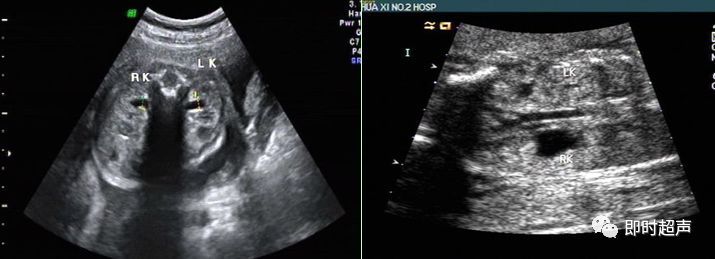

六、肾盂轻度分离(APD)

发生率为 0.59%~1.4%。可分为生理性肾积水和病理性肾积水

超声图像特点:胎儿肾盂轻度分离,肾皮质厚度变化不明显,双侧肾盂扩张程度相当,不伴输尿管扩张。

超声胎儿APD诊断标准

✔ 在任何孕龄肾盂前后径小于等于3 mm均属正常

✔ <32孕周肾盂前后径>4 mm

✔ >32孕周前后径>7 mm

✔ 任何孕周时前后径>10 cm

✔ >32孕周时APD为(5-8)mm,(9-15)mm,>15 mm,轻中重